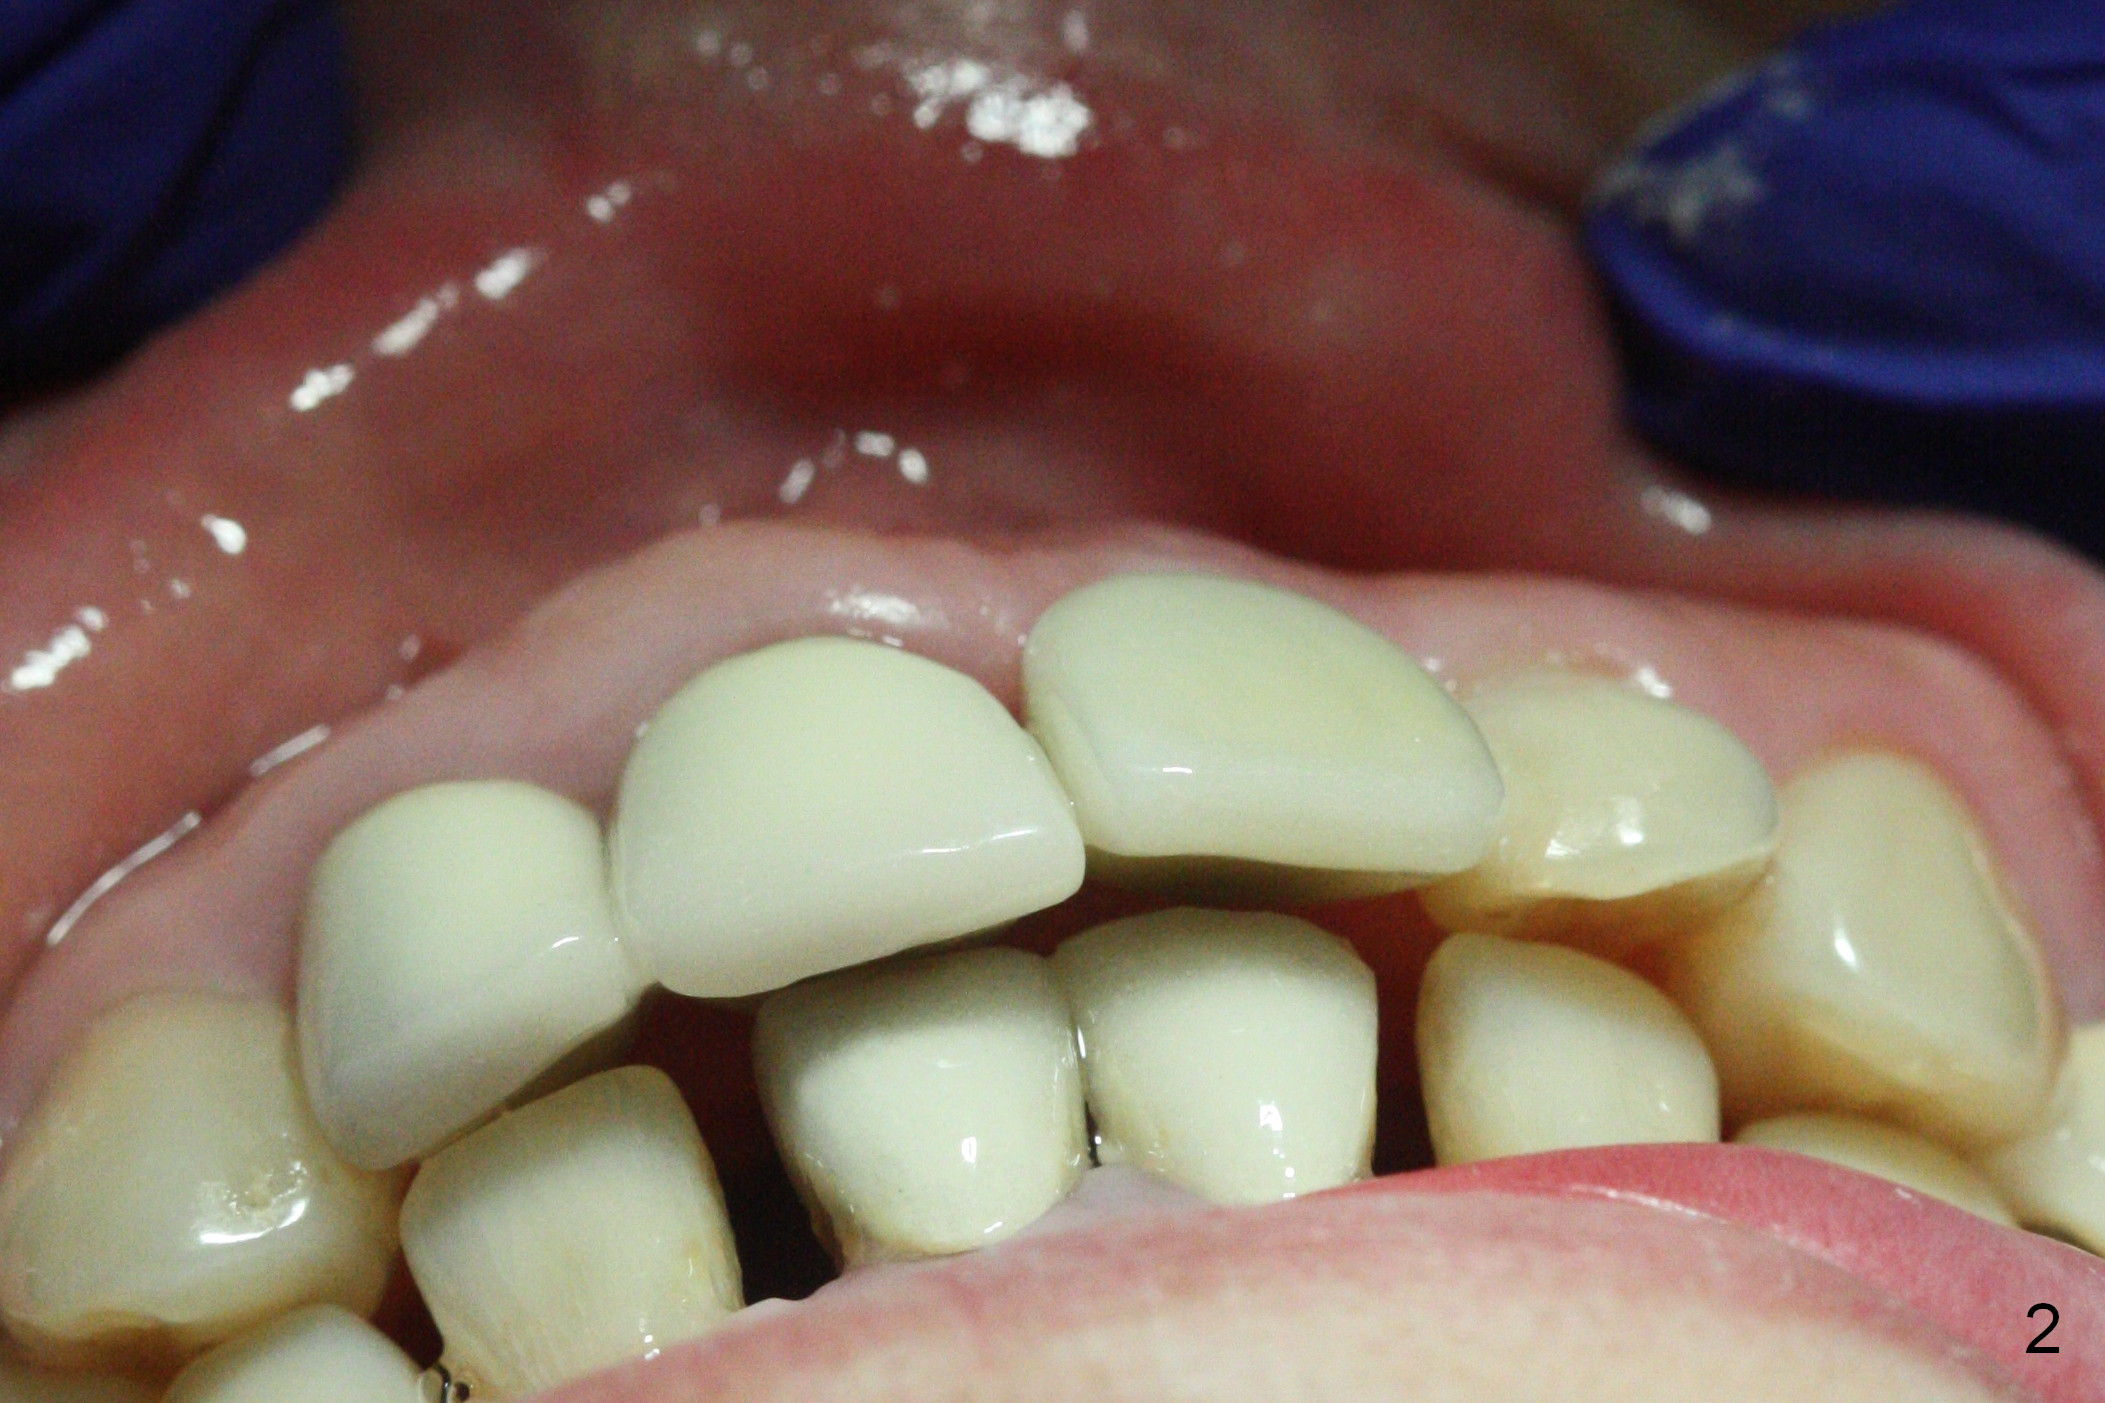

When a permanent crown (Fig.1 C) is seated 5 months postop, it looks too long and bulky (as well as metal show through cervically), which is in turn due to buccal placement of the crown (Fig.2) and abutment (Fig.3). By mistake, abutment is changed from 4.5x15°, 3 mm cuff to 4.5x15°, 2 mm cuff (Fig.4-6); the profile appears to improve. After prep (buccoincisal (Fig.4 ^) and linguoincisal), impression is taken. The gold coating in the buccocervical area is untouched so that there should be no or minimal metal show through. Please make a new crown as cosmetic as possible (not too bulky, especially buccocervical). If you feel that the result will be the same as before, return the case. The angled abutment may be changed 25°. In fact the new crown looks better.